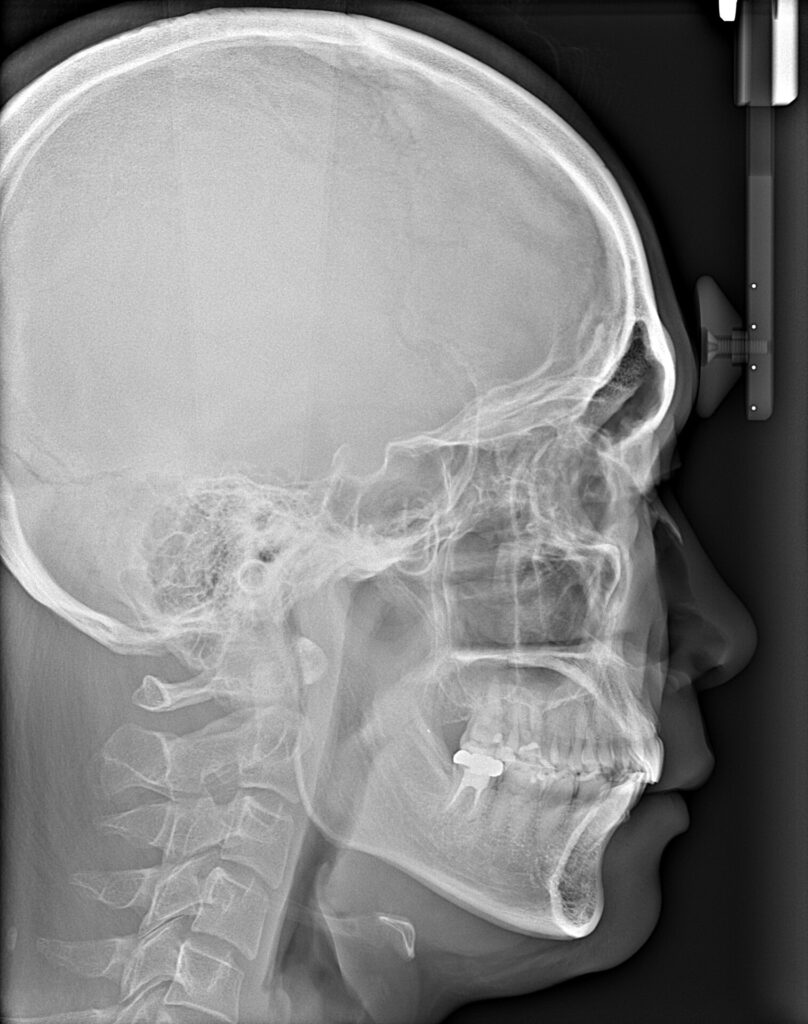

初回の無料カウンセリングで、「お口の中の写真」「横顔を含むお顔の写真」「レントゲン画像」などを撮影し、それらを元に、院長が一つひとつご説明します。

カウンセリングでは、お悩みやご希望など、どんな些細なことでもお伺いしております。検査では、口腔内検査の他にレントゲン撮影、3Dスキャン(歯の型取り)をします。